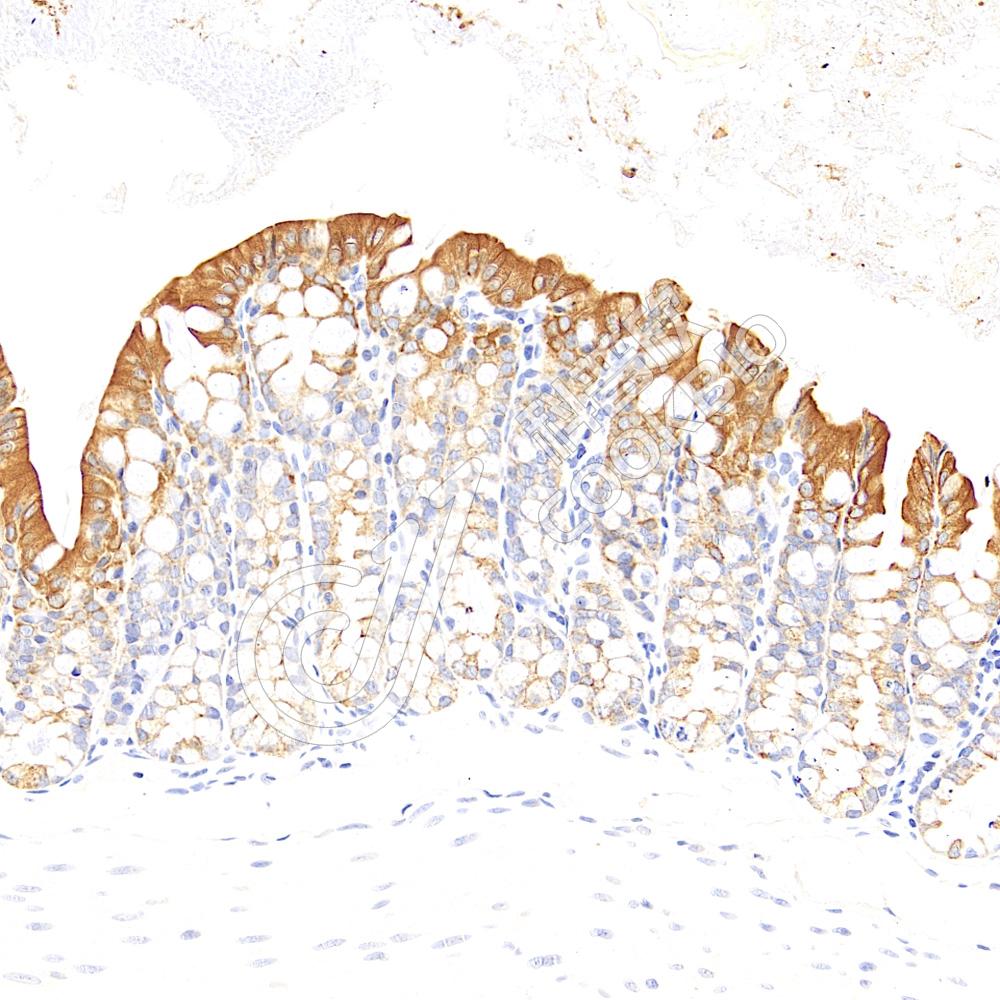

IHC检测E-cadherin蛋白(货号 K236249).

样品: 小鼠结肠, 4%多聚甲醛 (货号KSG1101) 固定12-24小时.

抗原修复: 柠檬酸抗原修复液(干粉, pH 6.0) (KSG1201), 高压锅均匀喷气计时2分钟.

—抗: 1: 2800稀释, 4℃ 孵育过夜.

二抗: S-vision免疫组化多聚二抗(山羊抗小鼠), 即用型(货号KB3903), 室温孵育20分钟.